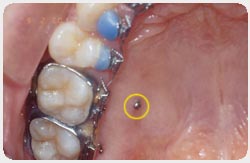

Procedura de inserare este una foarte simpla si consta in anestezie locala prin infiltratie, urmata de inserarea mini-implantului. Intreaga procedura dureaza intre 5 si 10 minute dupa instalarea anesteziei. Singura parte vizibila a mini-implantului este capul acestuia ce serveste ca punct de ancoraj in transmiterea fortelor ortodontice.